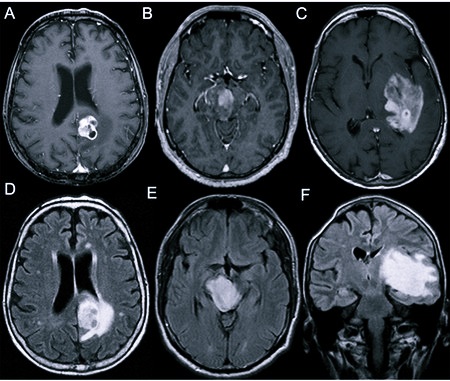

- МРТ – показывает опухоль в любой точке мозга, помогает рассчитать ее размер с точными контурами, для повышения эффективности исследования пациенту в вены вводят контрастное вещество;

- КТ – отображает отделы мозга, четко показывает все особенности найденной опухоли, включая ее границы с точным строением;